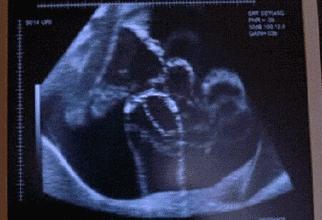

胎动影像